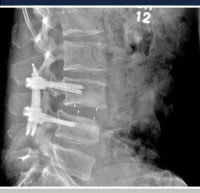

Minimally invasive techniques may be used to address many pathologic conditions of the spine, including those secondary to degenerative problems, deformity, tumors, infection and trauma. In general, pathologic conditions of the spine can be addressed through anterior, posterior or combined (anterior and posterior) surgical approaches. Advances in minimally invasive surgery have led to improvements with the utilization of each of these approaches. For example, anterior approaches in general can be less invasive with respect to the spine itself as the spinal nerves are not manipulated and the important muscles of the posterior spine are not disturbed. Advances in spinal instrumentation, retractor systems, video technology and instruments have led to further advances in anterior spinal surgery by allowing the utilization of “mini-open” approaches or laparoscopic techniques in certain conditions, combining anterior approaches with minimally invasive posterior instrumentation may allow the benefit of addressing the anterior pathologic condition via the most direct approach, while maximizing spinal stability through the utilization of spinal instrumentation that does not significantly disrupt then posterior spinal musculature. Also, with the appropriate diagnosis and indication, minimally invasive posterior approaches may allow for both anterior and posterior spinal pathology and spinal stability to be addressed through multiple, small, posterior incisions, utilizing special retractor systems and intra-operative fluoroscopic imaging.